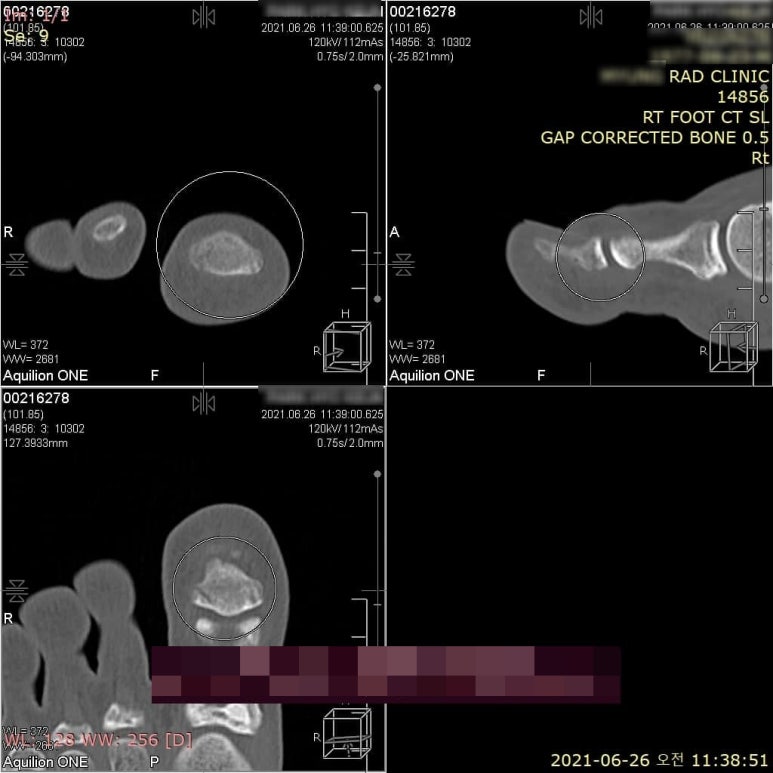

특히 다친 직후에 검사하면 골절선이 잘 보이지 않습니다. 처음에는 어긋나지 않았더라도 5-7일 정도 지나면 출혈과 부종이 생기고 골절부위가 살짝 벌어지기 때문에 좀 더 쉽게 찾을 수 있습니다.만약 접질린 후 1주일간 절대 안정을 취했는데도 전혀 호전이 없다면 골절을 의심해봐야 합니다. 아래 환자분은 서울 강서구 화곡동에서 엄지발가락 타박상 이후 엑스레이상 골절을 발견하지 못하고 침 치료를 하고자 한의원에 오신 분입니다.

걷는데 전혀 지장이 없고 엄지발가락에 힘이 들어갈 때만 아프다고 합니다.** 꼼꼼하게 진료해보니 골절이 의심되었고, 640 CT 검사를 의뢰하였습니다.

협력병원에서 CT 검사상 비전위성 골절로 진단 받으셨습니다.이렇게 위치는 거의 그대로 유지하면서 뼈가 똑 부러진 경우, 엑스레이에서 골절이 잘 보이지 않습니다.

위 환자분은 화곡역 계단에서 발목을 접질린 후 오전 10시33분에 동네 정형외과에서 엑스레이를 찍으셨습니다. 엑스레이상 골절은 없고 인대가 늘어났다고 하여 한의 치료를 받고자 오셨습니다. 걷는데는 전혀 불편함이 없고, 계단을 딛거나 힘이 들어가면 아픕니다. 펜으로 표시한 부위가 다친 부위인데, 눌러보니 자지러지게 아프다고 합니다.

이 곳은 종골의 전방 돌기로 종입방골인대가 붙는 곳입니다. 종입방인대 앞쪽섬유는 두갈래인대(종입방인대 + 종주상인대) 중 하나인데, 여기 인대가 당겨지면서 작은 견열골절이 발생하면 엑스레이에서 골절선이 잘 보이지 않습니다. 확실하게 골절 여부를 확인하기 위해 640 CT를 의뢰하였습니다.

바로 협력병원으로 전원시켜 시행한 640시티에서 종골 전방 돌기의 견열골절로 진단되었습니다.위 그림의 우측 시티에서는 골절이 보이지만 좌측 엑스레이에서는 뼈가 겹쳐서 골절선이 보이지 않습니다. 떨어져 나간 뼈 조각은 본래 뼈와 붙지 않고 인대 내부에 남아있게 됩니다.** > 수술을 꼭 해야 하나요? 골절 부위와 형태, 전위 정도, 관절 침범 여부에 따라 다릅니다. 예를 들어 손목의 주상골 골절(scaphoid fracture)도 엑스레이에서 잘 보이지 않습니다. 그런데 문제는 여기에 골절이 생기면 뼈가 유합되지 않고 괴사되는 경우가 많습니다.**